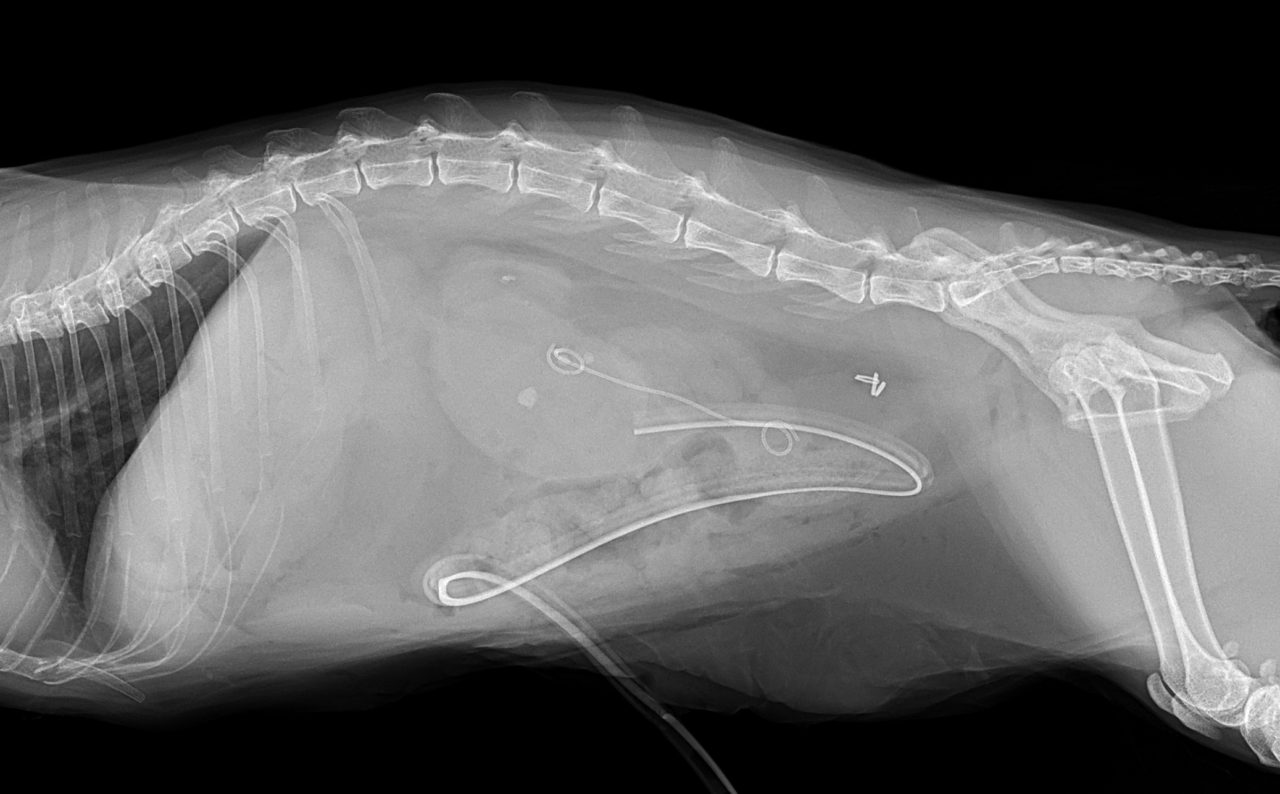

尿管結石による急性の腎障害で腎数値が顕著に上昇しているというマンチカンちゃんが手術のために来院しました。CTで確認すると複数個の結石が尿管内に存在しています。この問題に対して顕微鏡下で尿管膀胱新吻合と短尺型(カスタムメイド)尿管ステントを設置しました。36時間後には腎数値も改善しました。長時間の手術となりましたがよく頑張ってくれました。